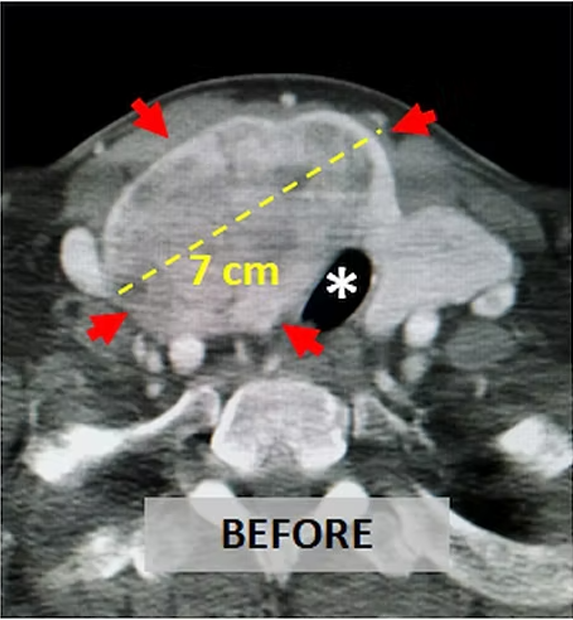

The thyroid gland has generally four feeding arteries and they also supply four parathyroid glands. This, to prevent hypothyroidism and hypoparathyroidism, 2 or 3 out of 4 feeling vessels are embolized and at least one vessel is left intact. If both thyroid lobes require treatment, embolization can be done first to one lobe, and some months later, to the other lobe. After the embolisation, the thyroid nodules become dead and shrink rapidly. If there is hyperthyroidism as in Graves disease or toxic nodule(s), the TSH, T3 and T4 labels either improve or return to normal. After the embolisation, patients may experience some neck pain and temporary hyperthyroidism for some weeks.

In thyroid diseases, the most common treatments are surgery RAI and percutaneous ablation. Embolisation is performed in patients who are not suitable for or do not desire these treatments. For example, in large plunging goiters, surgery is generally difficult since anesthesia is challenging and chest must also be opened besides the neck. In such cases, embolisation may be done easily and effectively. After the procedure, the goiter may become smaller and compressive symptoms such as shortness of breath, swallowing difficulty hoarseness may improve. In Graves disease similarly, embolisation results in lowering or normalization of thyroid hormones in more than 70% of the cases. If the hyperthyroidism is caused by nodule(s) in a MNG patient, embolization can not only make the nodule(s) smaller also correct the hyperthyroidism. Similarly, in patients with a single large (more than 6 cm) nodule, embolisation of the nadule is very effective in reducing its size. In such large nodules, percutaneous ablation is generally not very effective.